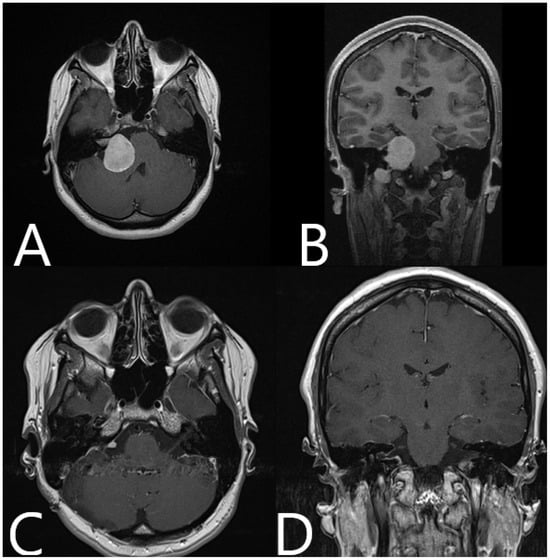

Illustrative Cases